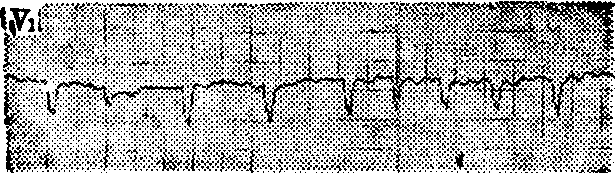

图1 心房扑动2:1心电图

心房扑动: 无P波,以F波代之,频率每分钟250~350次、间距均匀、波形一致并连续成锯齿状,无等电位线;QRS波群呈室上型; 由于不同比例的房室传导,心室率往往较心房率慢,节律规则或不规则。如F波的间距与形状略有差异,且频率每分钟>300次者,称不纯性房扑或心房扑动颤动。